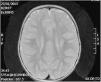

A magnetic resonance imaging (MRI) scan performed at age 2 years found myelination defects (Fig. 2). Currently, at age 6 years, the patient has mild intellectual disability and axial hypotonia with spasticity in the lower extremities that precludes independent walking.

Patients 2 and 3 are sisters in a family with no known consanguinity. At birth, at 34 and 36 weeks’ gestation, respectively, both presented with moderate ichthyosis described as “lamellar”. They developed the ability to sit at around 9 months and independent walking between ages 4 and 6 years. Patient 2 retains independent walking at age 22 years. Both sisters developed signs of spasticity in the first 2 years of life, and Sjögren-Larsson syndrome was suspected due to the detection of myelination defects on neuroimaging.